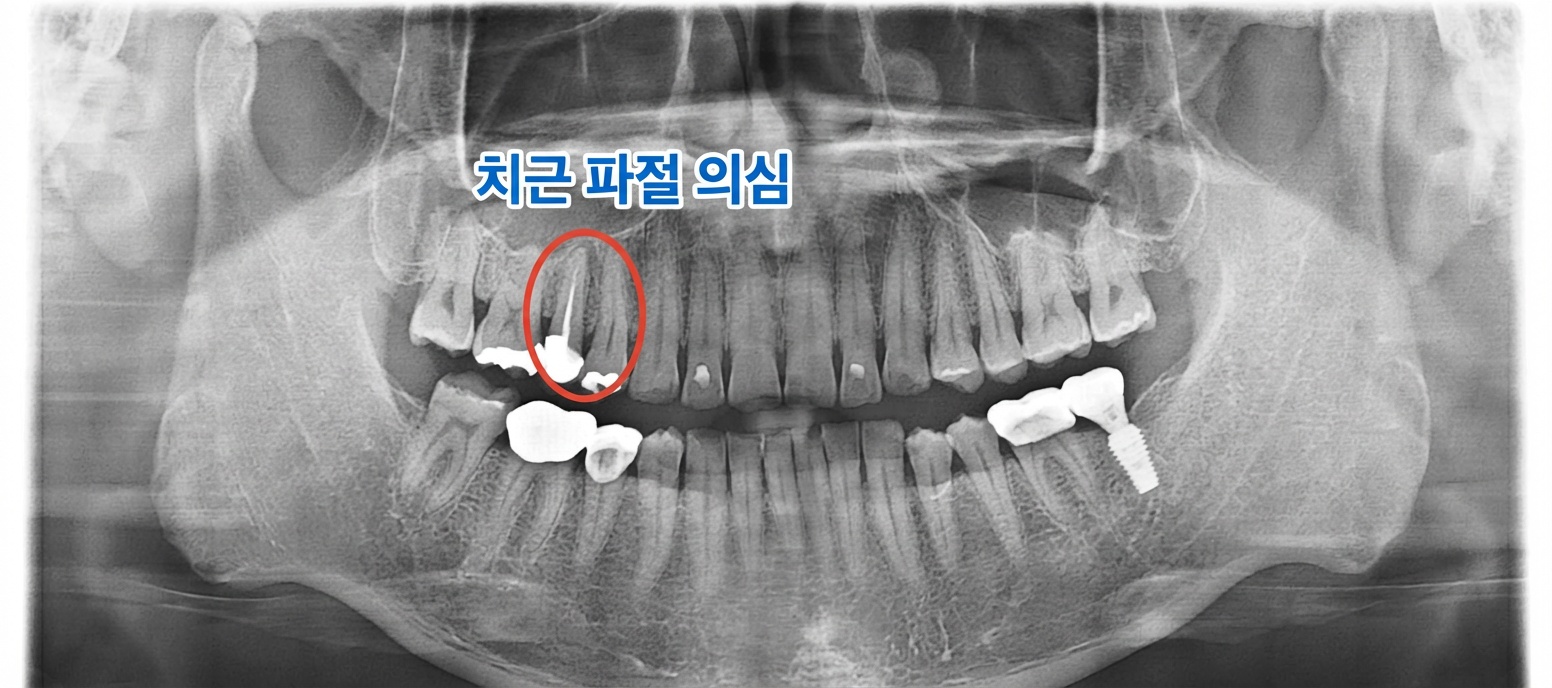

BEFORE 15번 치아 치근단 염증 상태

치료 전 : 15번 치아 치근단 염증 관찰 (촬영일: 2025.07.08)

위 어금니(#15)에서 수직 치근 파절과 함께 치근단 염증이 관찰되었습니다. 파절로 인해 자연치아 보존이 어려운 상태로 진단되었습니다.